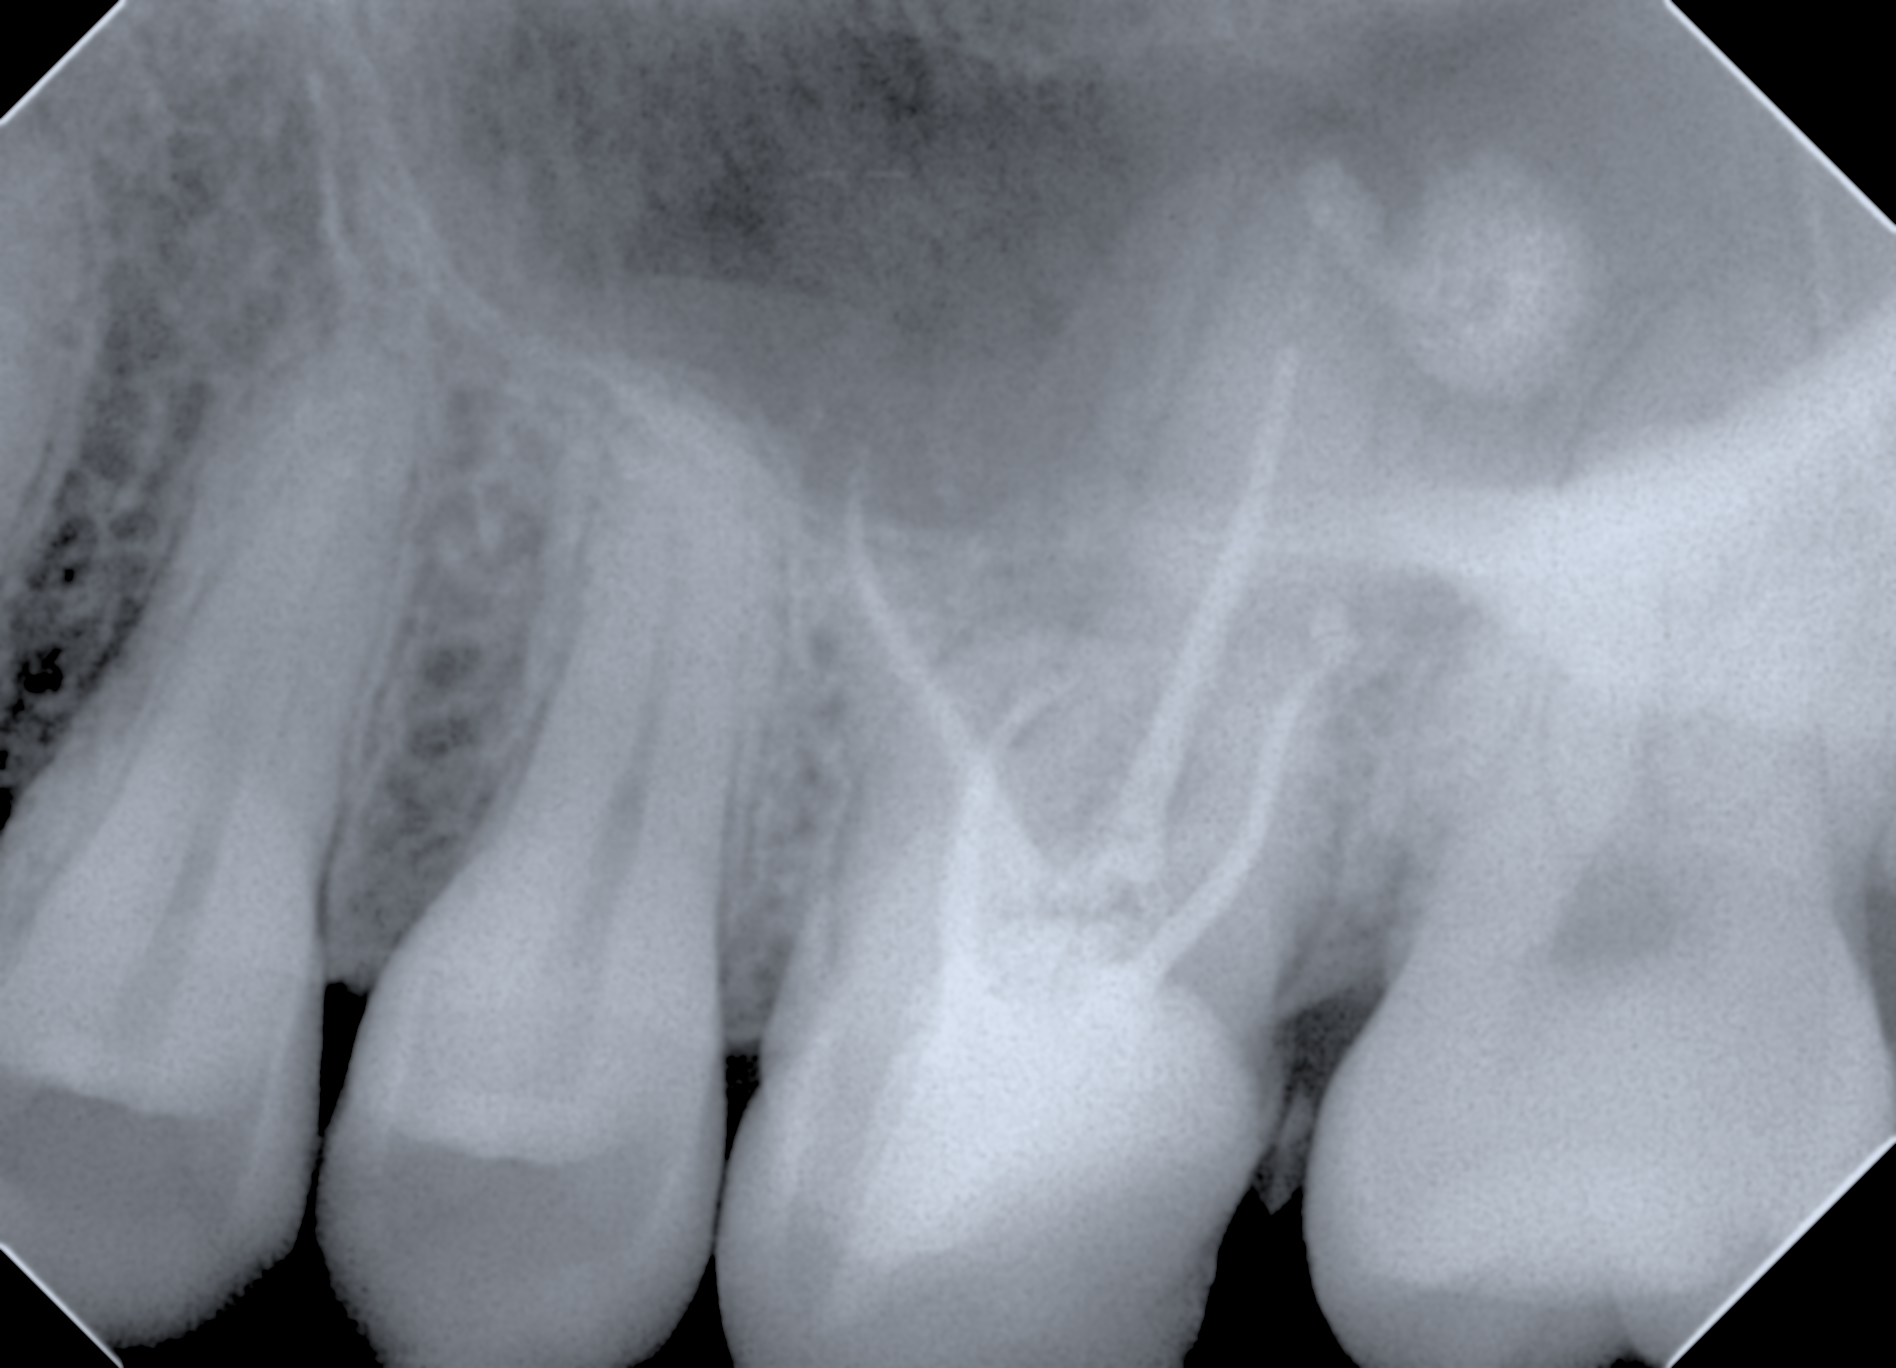

根っこは複雑です

歯の根っこは曲がっていたり、中で繋がっていたりさまざまな形をしています。

CTを撮影し、根管の形がどうなっているのかを精査し、顕微鏡(マイクロスコープ)を用いて治療を行なっていきます。(CTは5月末導入。マイクロスコープは7月末導入いたします。)